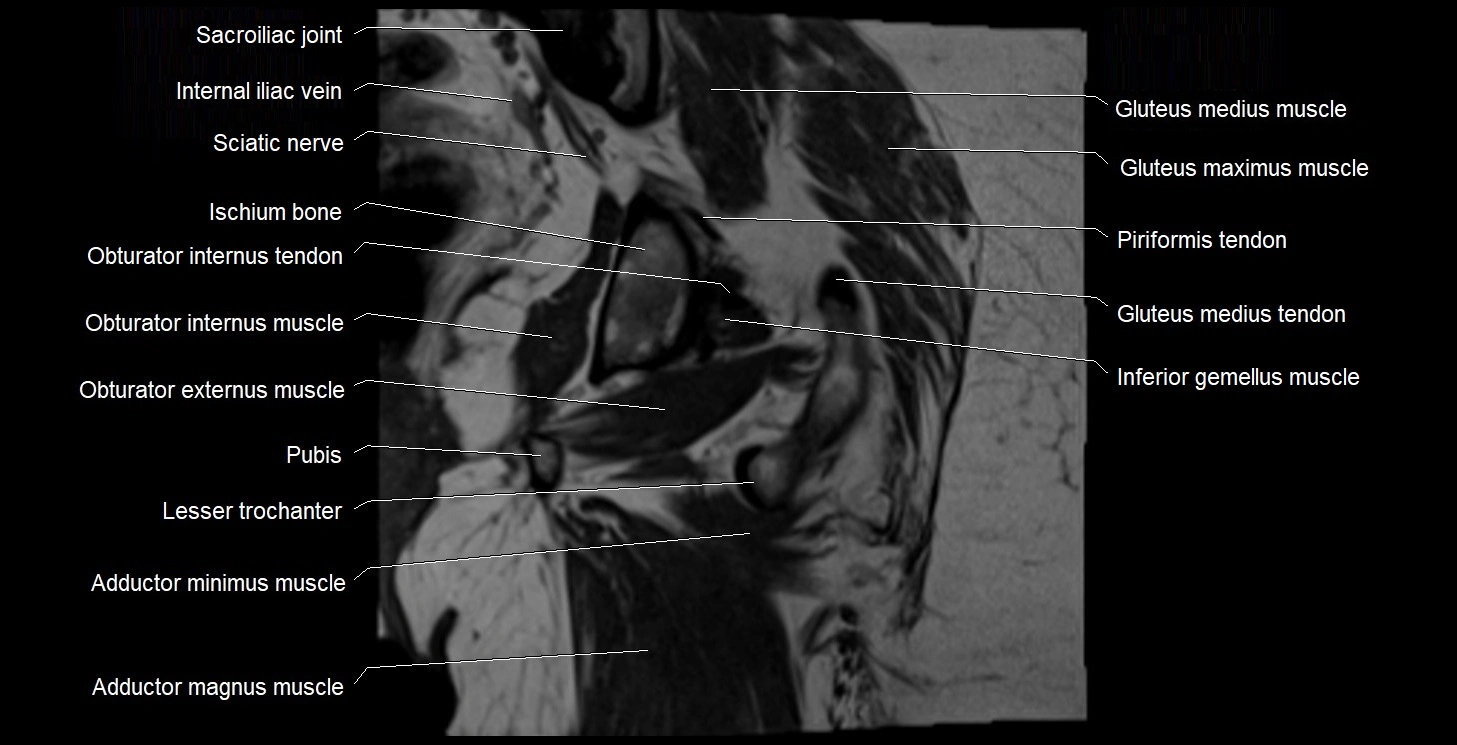

- Body of ischium

- Body of pubis

- Obturator internus muscle

- Obturator internus tendon

- Obturator externus muscle

- Gluteus medius muscle

- Gluteus maximus muscle

- Gluteus medius tendon

- Inferior gemellus muscle

- Lesser trochanter

- Sacroiliac joint

- Adductor brevis muscle

- Adductor magnus muscle

- Adductor minimus muscle